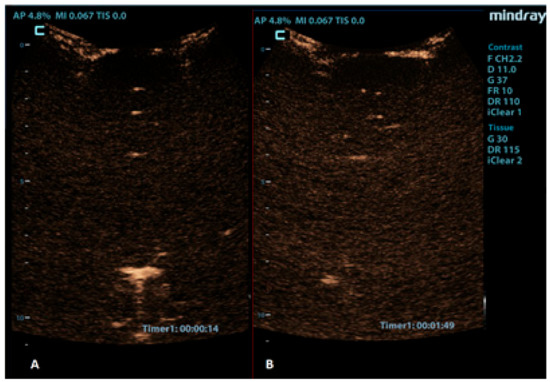

Brain death refers to the complete and irreversible loss of brain function, which is defined as the cessation of cortical and brainstem activities. Typically, the confirmation of brain death involves verifying three criteria: unconsciousness, the absence of brainstem reflexes, and apnea. However, the apnea test can be challenging to implement for infants and may pose risks to patients with unstable circulation. Therefore, various ancillary imaging tests can assist in making the diagnosis. Cerebral angiography and radionuclide scanning are commonly used on infants as ancillary imaging tests. However, they can be challenging to perform when the patient needs to be transported from an intensive care unit [80]. The bedside imaging test to confirm cerebral circulatory arrest is Doppler ultrasonography, which is used to evaluate the blood flow in intracranial and extracranial arteries. However, it may face challenges with transmission due to the inadequate penetration of ultrasound beams through the temporal bone, making the evaluation of intracranial vessels unreliable in some cases [81]. CEUSs allow the better visualization of cerebral vasculature compared to that of Doppler USs, and they also facilitate the evaluation of cerebral perfusion (Figure 7) [82]. Studies on adult populations have shown that the rate of inconclusive Doppler US examinations for determining cerebral circulatory arrest significantly decreases when CEUSs are performed [81,83]. A couple of reports already demonstrated that the CEUS can also be reliably used as an ancillary imaging test for the confirmation of brain death in neonates [37,84].

Figure 7.

Coronal CEUS images of a 1-year-old infant’s brain obtained (A) 14 s and (B) 109 s after the contrast administration. Both images demonstrate a lack of enhancement of the intracranial vasculature and no brain perfusion.